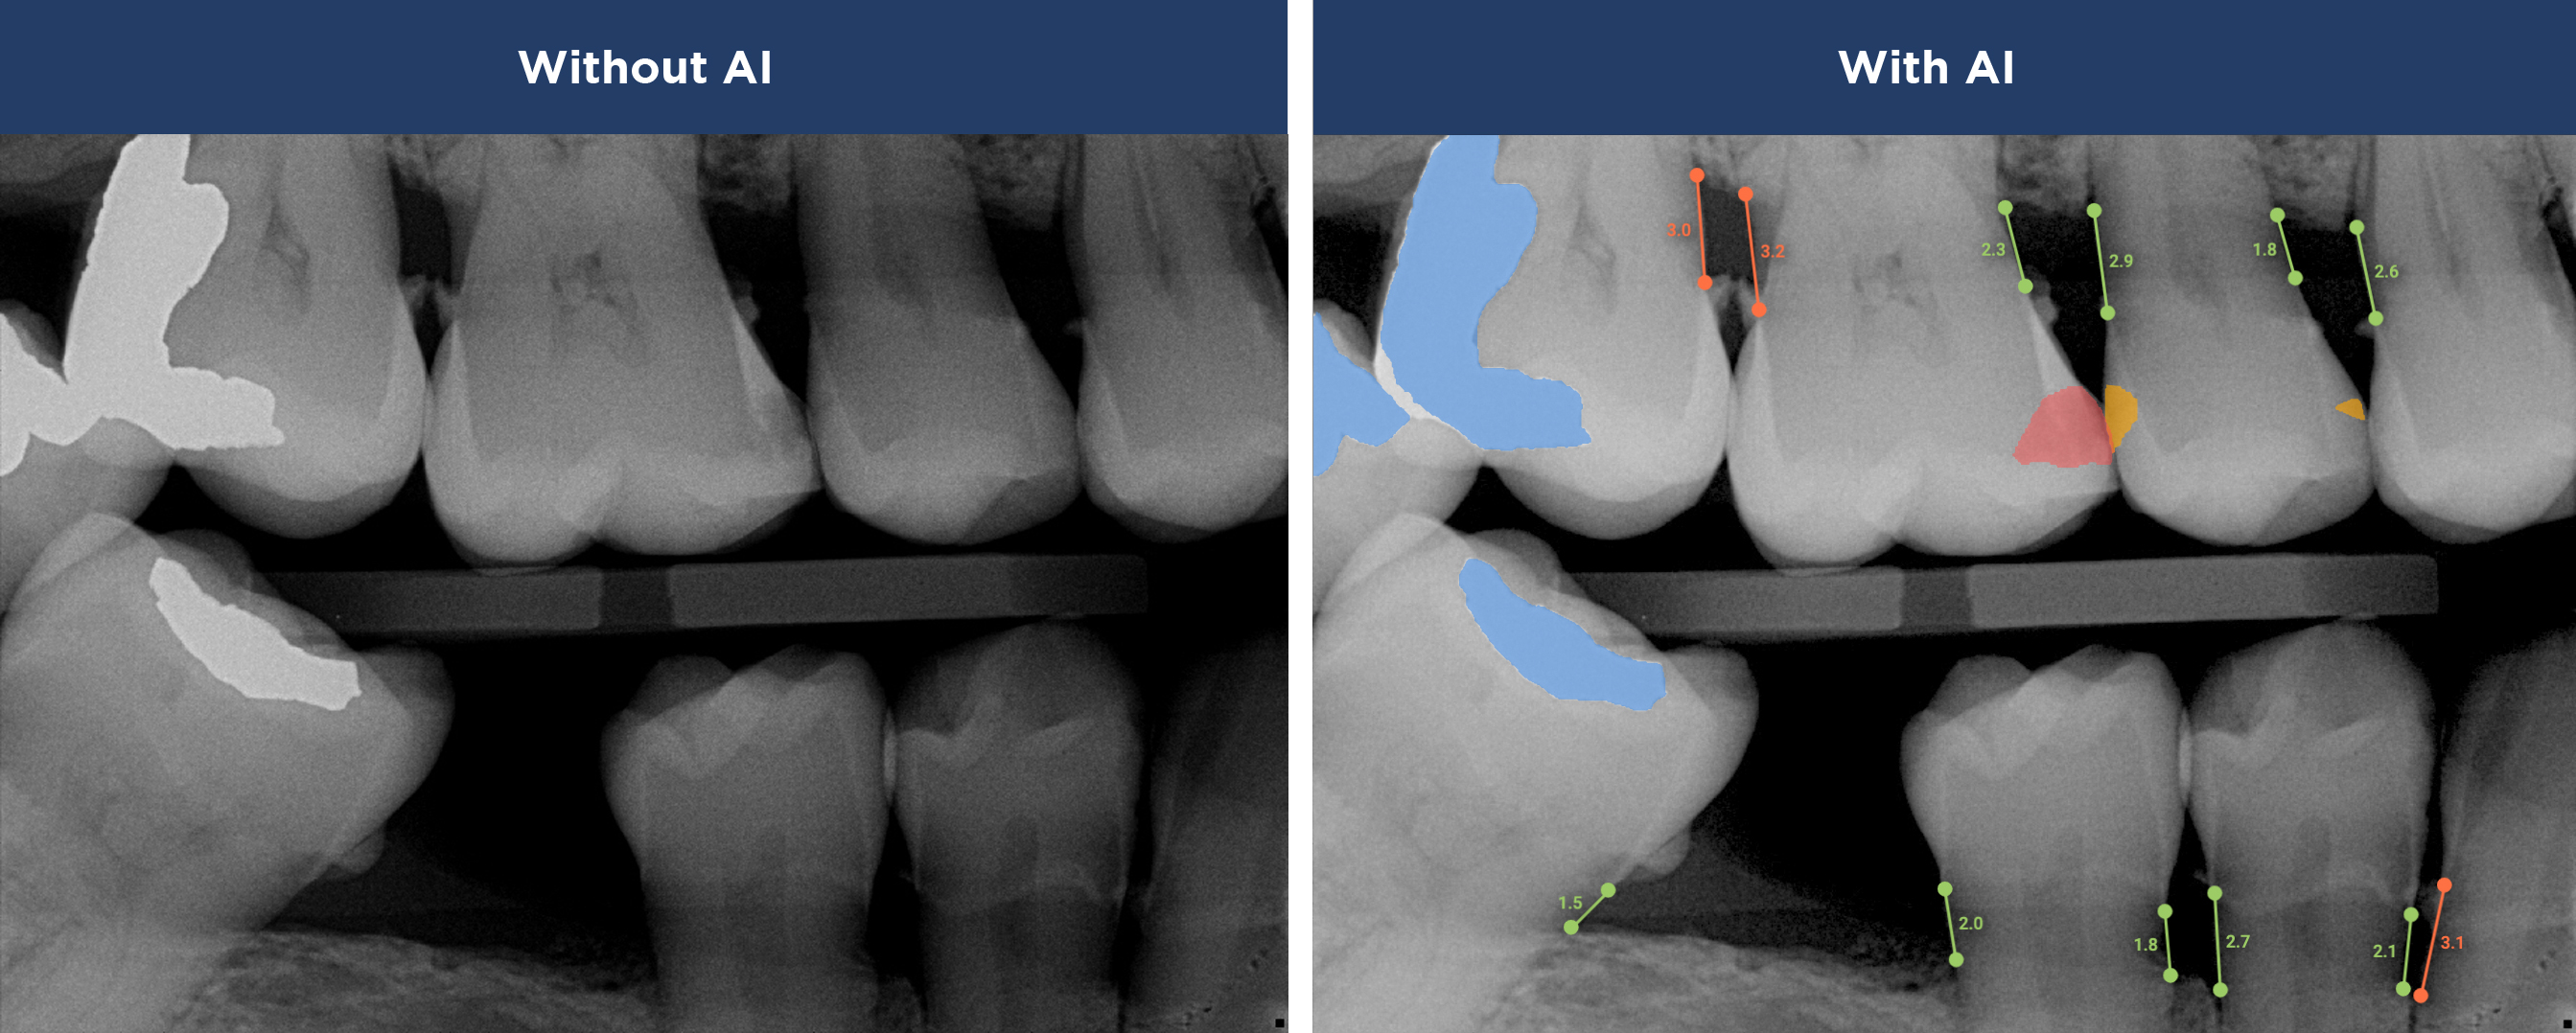

See More with AI

Overjet AI's  patient-centric technology combines human intelligence with the power of artificial intelligence.

Overjet’s artificial intelligence technology transforms traditional black-and-white X-rays by adding a layer of data that instantly outlines decay (cavities) and measures bone loss. This makes it easy for you to see your results alongside your dentist.  It’s like getting a second opinion delivered instantly. With Overjet’s analysis and easy-to-read presentation, you will have the information you need to make an informed decision about your oral health. Together, we’ll review your findings and discuss the best steps to take to achieve your goals.